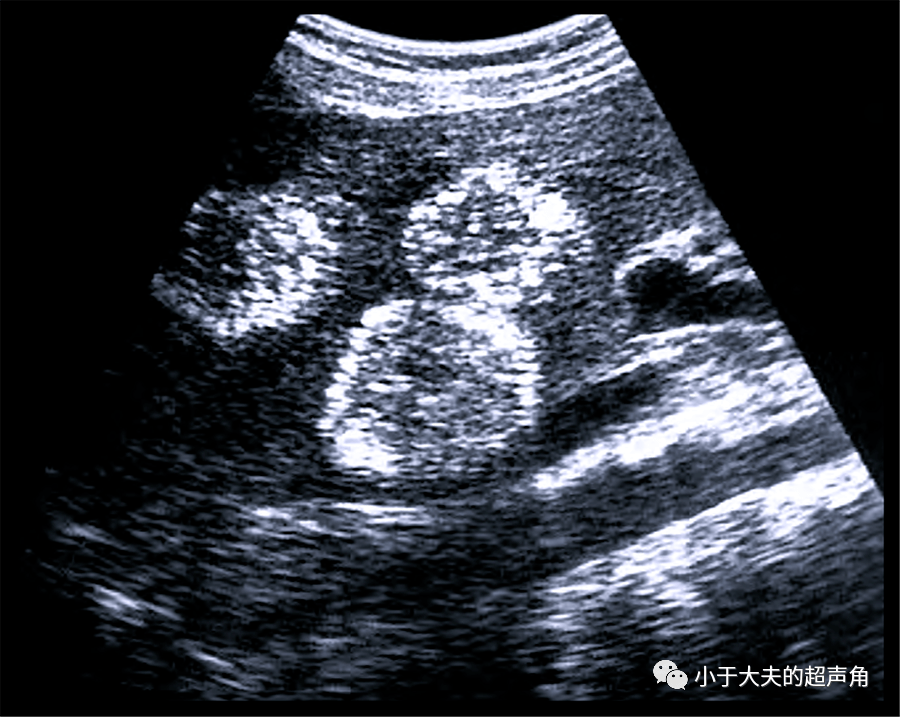

超声随响第28期肝紫癜症peliosishepatis